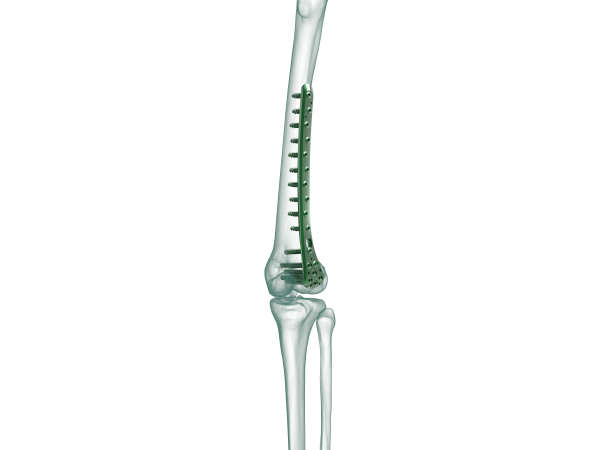

TRUE LOCK Distal Femur Lateral Anatomic Plate

TRUE LOCK Distal Femur Lateral Anatomic Plates are indicated for  fixation of fractions of the distal femur. Like; Distal diaphyseal fracture , intra-articular fracture , Supracondylar periprosthetic fracture.

Anatomical plate; right & left

10 hole options between 3-21

Optimized screw position in the condyles to avoid intercondylar notch and patellofemoral joint and maximize bone purchase.

Elongated Combi holes on shaft facilitate plate adjustment and allow locking or compression options.

Kirschner wire holes accept Kirschner wires (up to 2.0 mm) to temporarily fix the plate to the tibia , to temporarily reduce articular fragments, and to confirm the location of the plate, relative to the tibia.